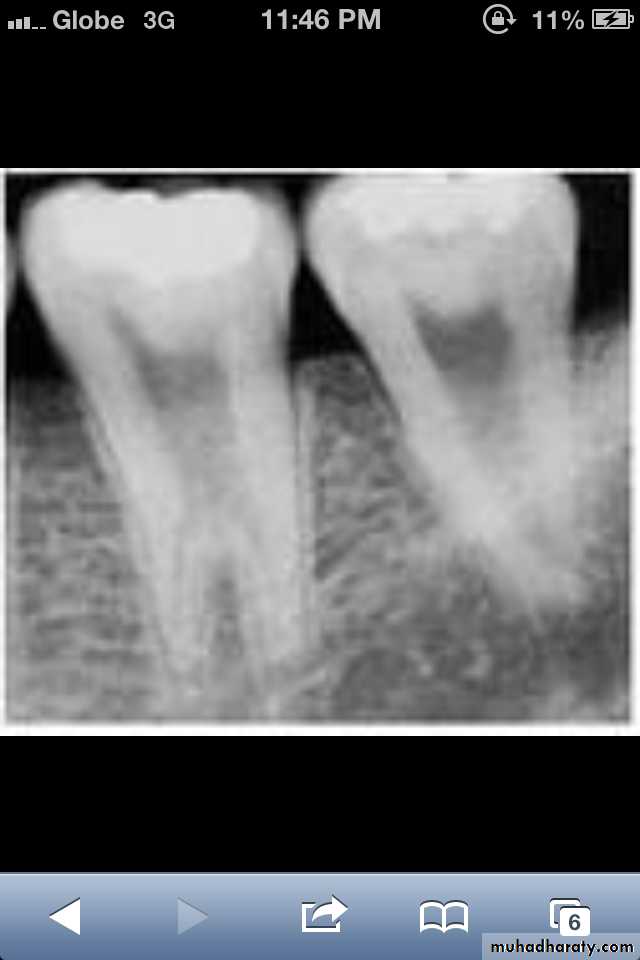

Radiographically:

Deciduous teeth:

roots are extremely short

pulps almost completely obliterated

Permanent teeth:

abnormally large pulp chambers in coronal portion of tooth.

Type II (Coronal Type)

Dentin dysplasia, type II. panoramic &periapical films of the same case show obliteration of the pulp chamber, reduction in the caliber of root canals, and pulp stones obscuring the flame-shaped pulp chambers.

Periapical inflammatory lesions are associated with some of the mandibular anterior teeth.